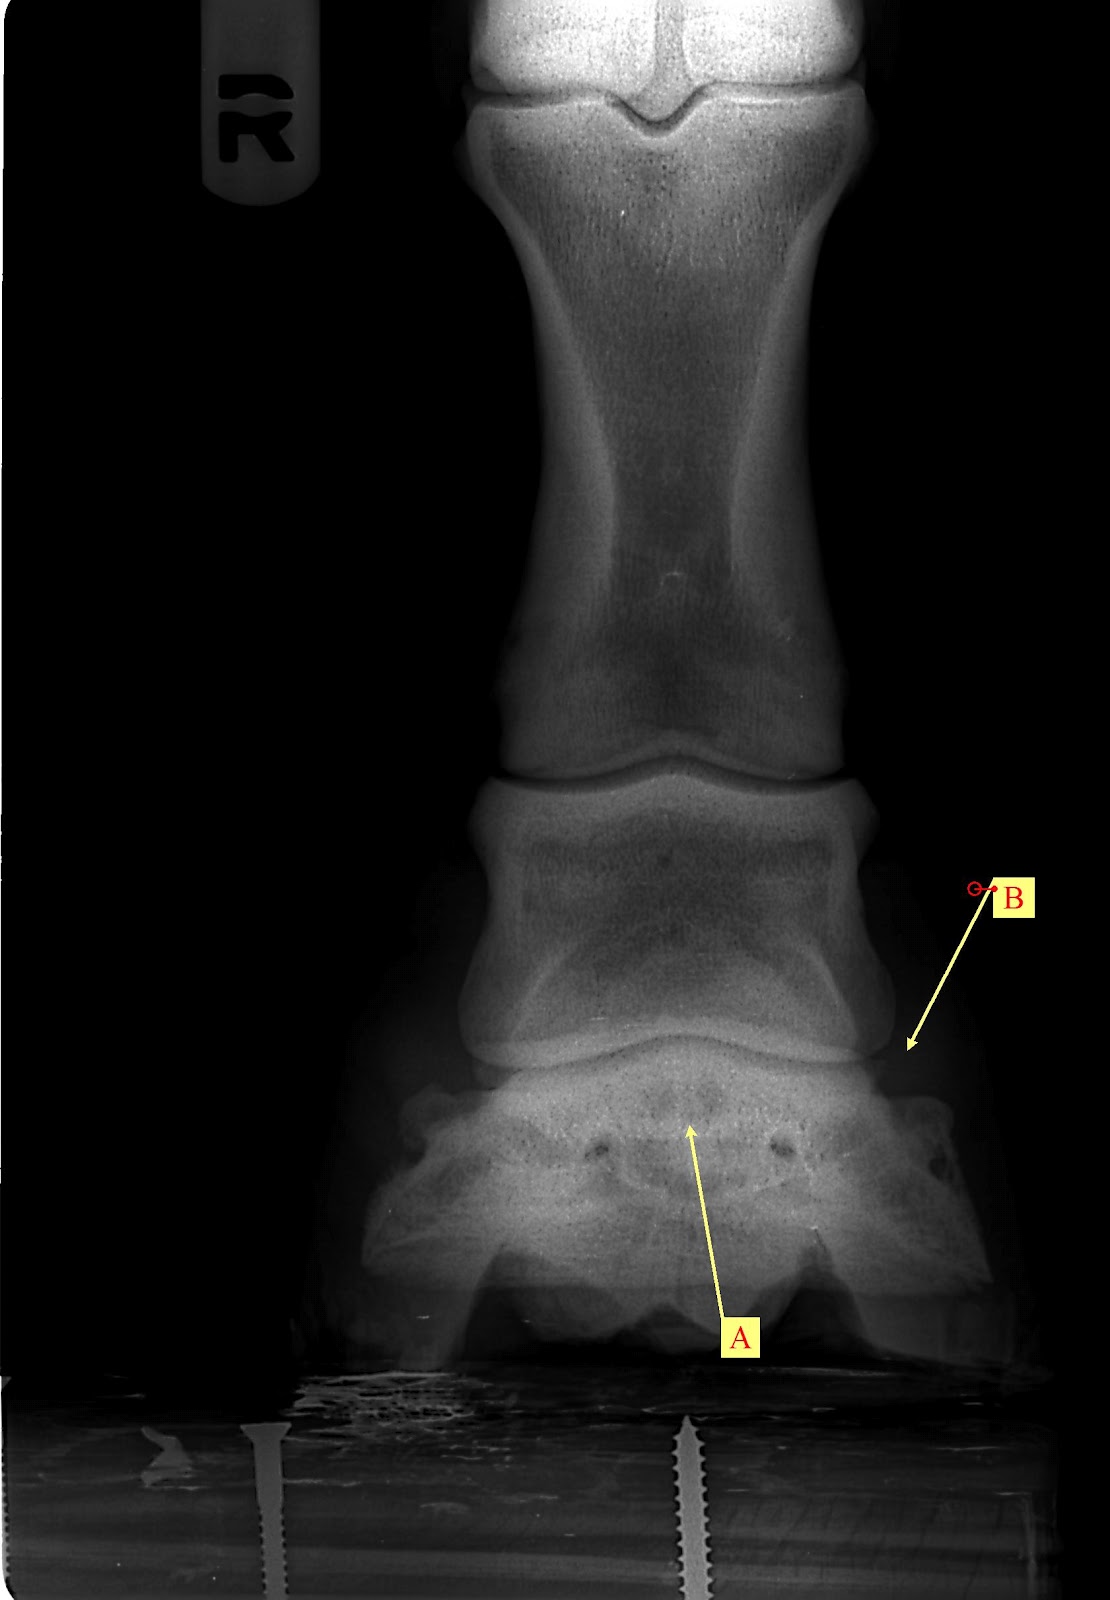

Horse Navicular X Ray . radiographs (x rays) are still important for examining the hoof’s bony structures and changes that are occurring. accurate radiographic evaluation of the navicular bone depends on a radiograph that is properly positioned and exposed and on a foot that is free of distracting artifacts. Many horses have pain in the heel region, which can be elicited by hoof testers. Radiographs will show any degenerative. However, researchers have found in. Abnormalities in the navicular bone navicular in horses relates to problems associated with the navicular bone in the horse’s hoof and is a common diagnosis for lameness in the front foot. Proper preparation for navicular radiography is similar to that for the distal phalanx, as discussed in chapter 23. a study looking at 72 horses that underwent mri for recent onset of navicular syndrome but without abnormalities detected on radiographs found the following: diagnostics involved in determining whether a horse has navicular syndrome include: Most horses show marked improvement in lameness with a palmar digital nerve block.

diagnostics involved in determining whether a horse has navicular syndrome include: radiographs (x rays) are still important for examining the hoof’s bony structures and changes that are occurring. navicular in horses relates to problems associated with the navicular bone in the horse’s hoof and is a common diagnosis for lameness in the front foot. Most horses show marked improvement in lameness with a palmar digital nerve block. Radiographs will show any degenerative. accurate radiographic evaluation of the navicular bone depends on a radiograph that is properly positioned and exposed and on a foot that is free of distracting artifacts. Abnormalities in the navicular bone Many horses have pain in the heel region, which can be elicited by hoof testers. However, researchers have found in. Proper preparation for navicular radiography is similar to that for the distal phalanx, as discussed in chapter 23.